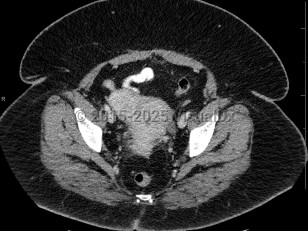

Uterine fibroids

Fibroids are often asymptomatic and may be only first noted incidentally on imaging done for other reasons, but patients can also present with abnormal bleeding, infertility, painful intercourse, constipation, increased pelvic or bladder pressure, urinary frequency, or rectal pressure.